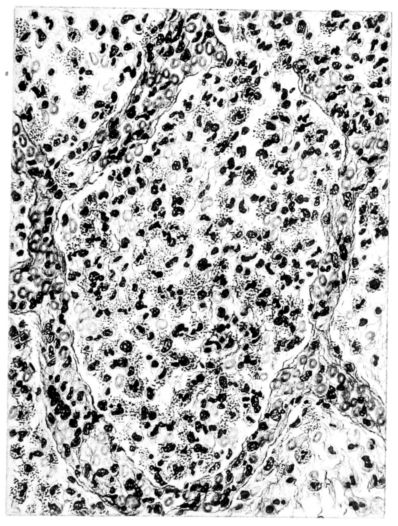

The changes are less marked, perhaps, in the trachea than in its finer ramifications. The mucosa is constantly more or less destroyed and large areas, usually focal, are entirely devoid of their epithelial covering. This is replaced by a sparse exudate, composed largely of red blood cells, mucus, a small amount of fibrin, and nuclear fragments (Fig. II). It may dip into the submucosa for a short distance, but usually these indentures are associated with the ducts of the mucous glands into which the inflammatory reaction extends. A more striking feature than the exudate, however, is the edema and the congestion of the submucosa. The loose areolar tissue of the submucosa is spread widely apart, and throughout it distended blood vessels are very conspicuous. Occasionally such a vessel is broken and actual hemorrhage appears in the submucosa. Occasionally, too, the inflammation extends down the duct to the mucous gland itself, and here, also, aplastic inflammatory reaction is evident, inasmuch as the acini now stain intensely red with the cells undifferentiated from each other and specked here and there by broken remains of the dead nuclei (Fig. III). After the disease has continued for a short period, even at the end of five or six days, some regeneration of the epithelial lining may be seen (3) (Fig. IV). But despite this, the acute picture persists, and there goes on, side by side, an attempted repair characterized by epithelial regeneration and the same evidence of acute change. Since the lesion is essentially a superficial one, scars or contractures of any extent are not encountered in the trachea, even in examples of the disease that have ended fatally only after many weeks.[4]

15There is considerable evidence to support the view that the disease spreads from bronchus to bronchus, and in keeping with this view, various stages in the inflammatory processes are more readily determined in these smaller structures than in the trachea. Furthermore, it must be emphasized that even the mildest and the most extreme of these stages are not infrequently encountered in the same lung. The earliest lesion is manifested by an increased homogeneity of the protoplasm of the epithelial lining of the bronchus. The cell protoplasm loses its normal granulation and the nucleus, somewhat darker than usual, becomes conspicuous on a red base (Fig. V). In the lumen of such a tube a serous exudate, perhaps mixed with mucus, is encountered, and there is some spreading apart of the surrounding muscular tissue with engorgement of the vessels. This picture merges gradually into one where the epithelium appears as a homogeneous, red-staining ribbon, devoid of nuclei, often exfoliated, in part at least, from the underlying submucosa (92). The change is traceable through the larger bronchi, even to the ducti alveolares, and not infrequently, bacteria, either as a diffuse, minute dotting or in the form of circumscribed, colony-like formations, are spread through the red, ribbon-like strand (Fig. XVI). With the exfoliation of the epithelial lining, the submucous vessels become more and more conspicuous and may bulge into the lumen of the tube (Fig. VI). That they actually weep into the lumen is proved by the presence of red blood cells in the exudate, now rich in mucus, broken-down nuclei, and desquamated cells. The necrotizing process may not extend deeper than the epithelial lining as is the status described above (140, 162), but it also frequently involves the underlying submucous and muscular layers, so that these lose their identity and stand out as homogeneous masses, in which fragmented nuclei and bacterial accumulations are prominent. Such deeper necrotizing areas may be focal (Fig. VII), or may involve the entire circumference of the tube (Fig. VIII). Occasionally, the epithelium, now dead and staining homogeneously, is lifted from the underlying submucosa in the form of a blister (66), and has very much the same appearance as the well known, early reaction which follows the application of croton oil to the rabbit’s ear. Where this occurs, the submucosa is less involved, as though the necrotizing agent had not penetrated to the same depth and the serous reaction beneath were actually a beneficent exudate. These blisters are in contrast with the deeper areas where the fibrinous mass, mixed with the dead tissue, forms an intensely staining ring or band, which extends through the bronchiolar wall even to the surrounding alveoli.

In the early stage of this process one of the most outstanding features is the absence of polynuclear leucocytes in the reactionary process, but gradually as the dead tissue sloughs away, these cells wander into the exudate and form a purulent ring, more intense in the lumen, but extending for a variable distance through the still viable wall of the structure (47) (Fig. IX). Later mononuclear cells accumulate in this wall and occur either as a diffuse mottling or as circumscribed foci in the muscle and submucous layer of the bronchiole, just as they do in the trachea. Occasionally, a striking change is found in a small bronchiole within a portion of the lung which is otherwise uninvolved by an inflammatory process. Perhaps the alveoli were the seat of a change which has subsided, but, whatever the history, the purulent mass in the bronchiole and involving its wall, stands out effectively (Fig. X).